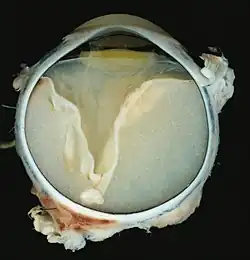

Как правило, макроскопически видны отслоение сетчатки и желтоватый субретинальный экссудат, содержащий кристаллы холестерина.

Микроскопически, стенки сосудов сетчатки могут утолщаться в некоторых случаях, в то время как в других случаях стенки может быть истончены с нерегулярным расширением просветов[11]. Субретинальный экссудат состоит из кристаллов холестерина, макрофагов, нагруженных холестерином и пигментом, эритроцитов, и гемосидерина[12]. Гранулёматозную реакцию, индуцированную экссудатом, может быть видно в сетчатке[13]. Фрагменты сетчатки могут развивать глиоз в ответ на повреждение.